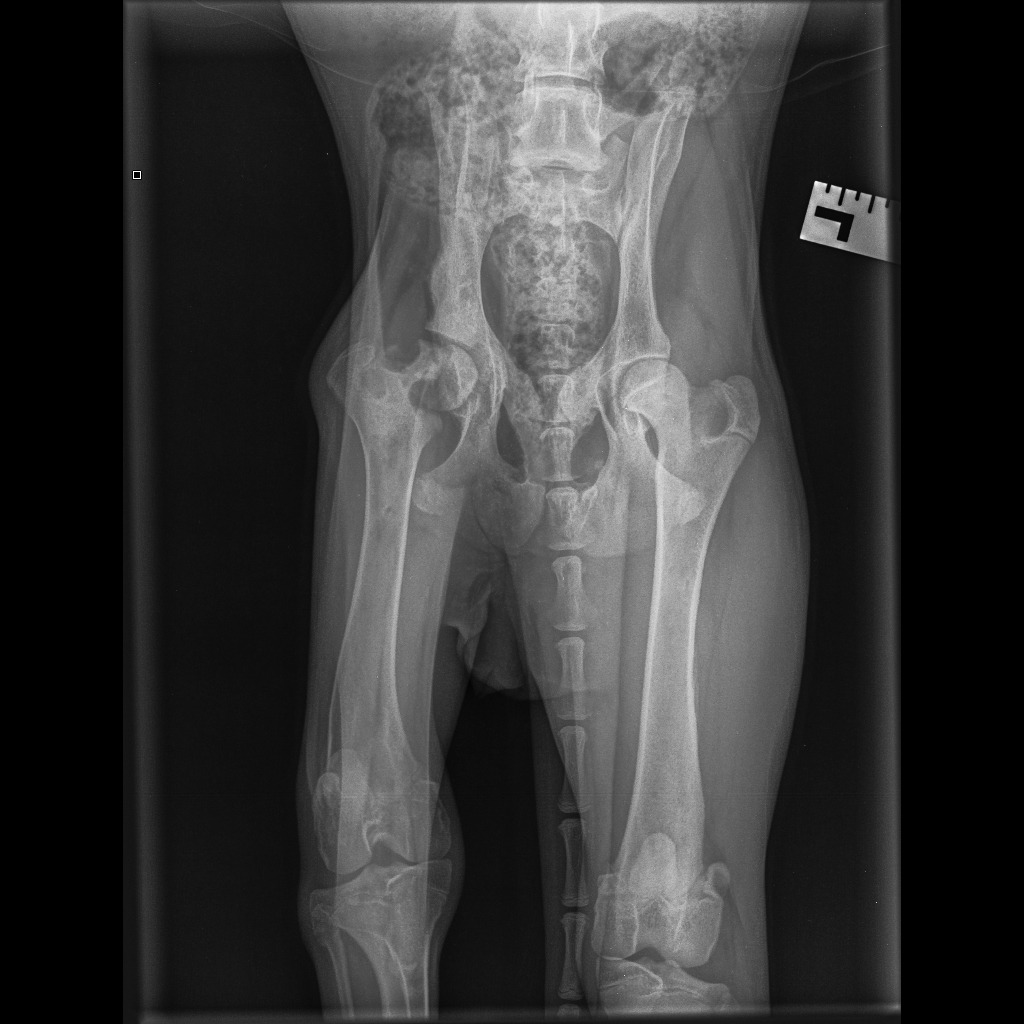

The surgery will only go ahead with a 50% deposit paid on the morning of the procedure, with the remaining balance due at discharge. Biggie is in severe, unmanageable pain, and the vet’s assessment is that the only remaining options to this surgery is immediate euthanasia – or a total hip replacement that is four times more expensive. Attached are the surgery estimate (to be paid), pre-evaluation and medication costs (already paid), and X-ray images.